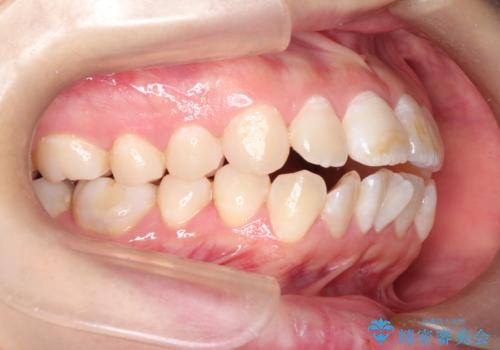

- ”口元を下げたい”が主訴で来院されました。

抜歯してワイヤー矯正を行い、口元も改善され大変満足していただきました。

小臼歯の抜歯を行うことで口元を改善することができました。